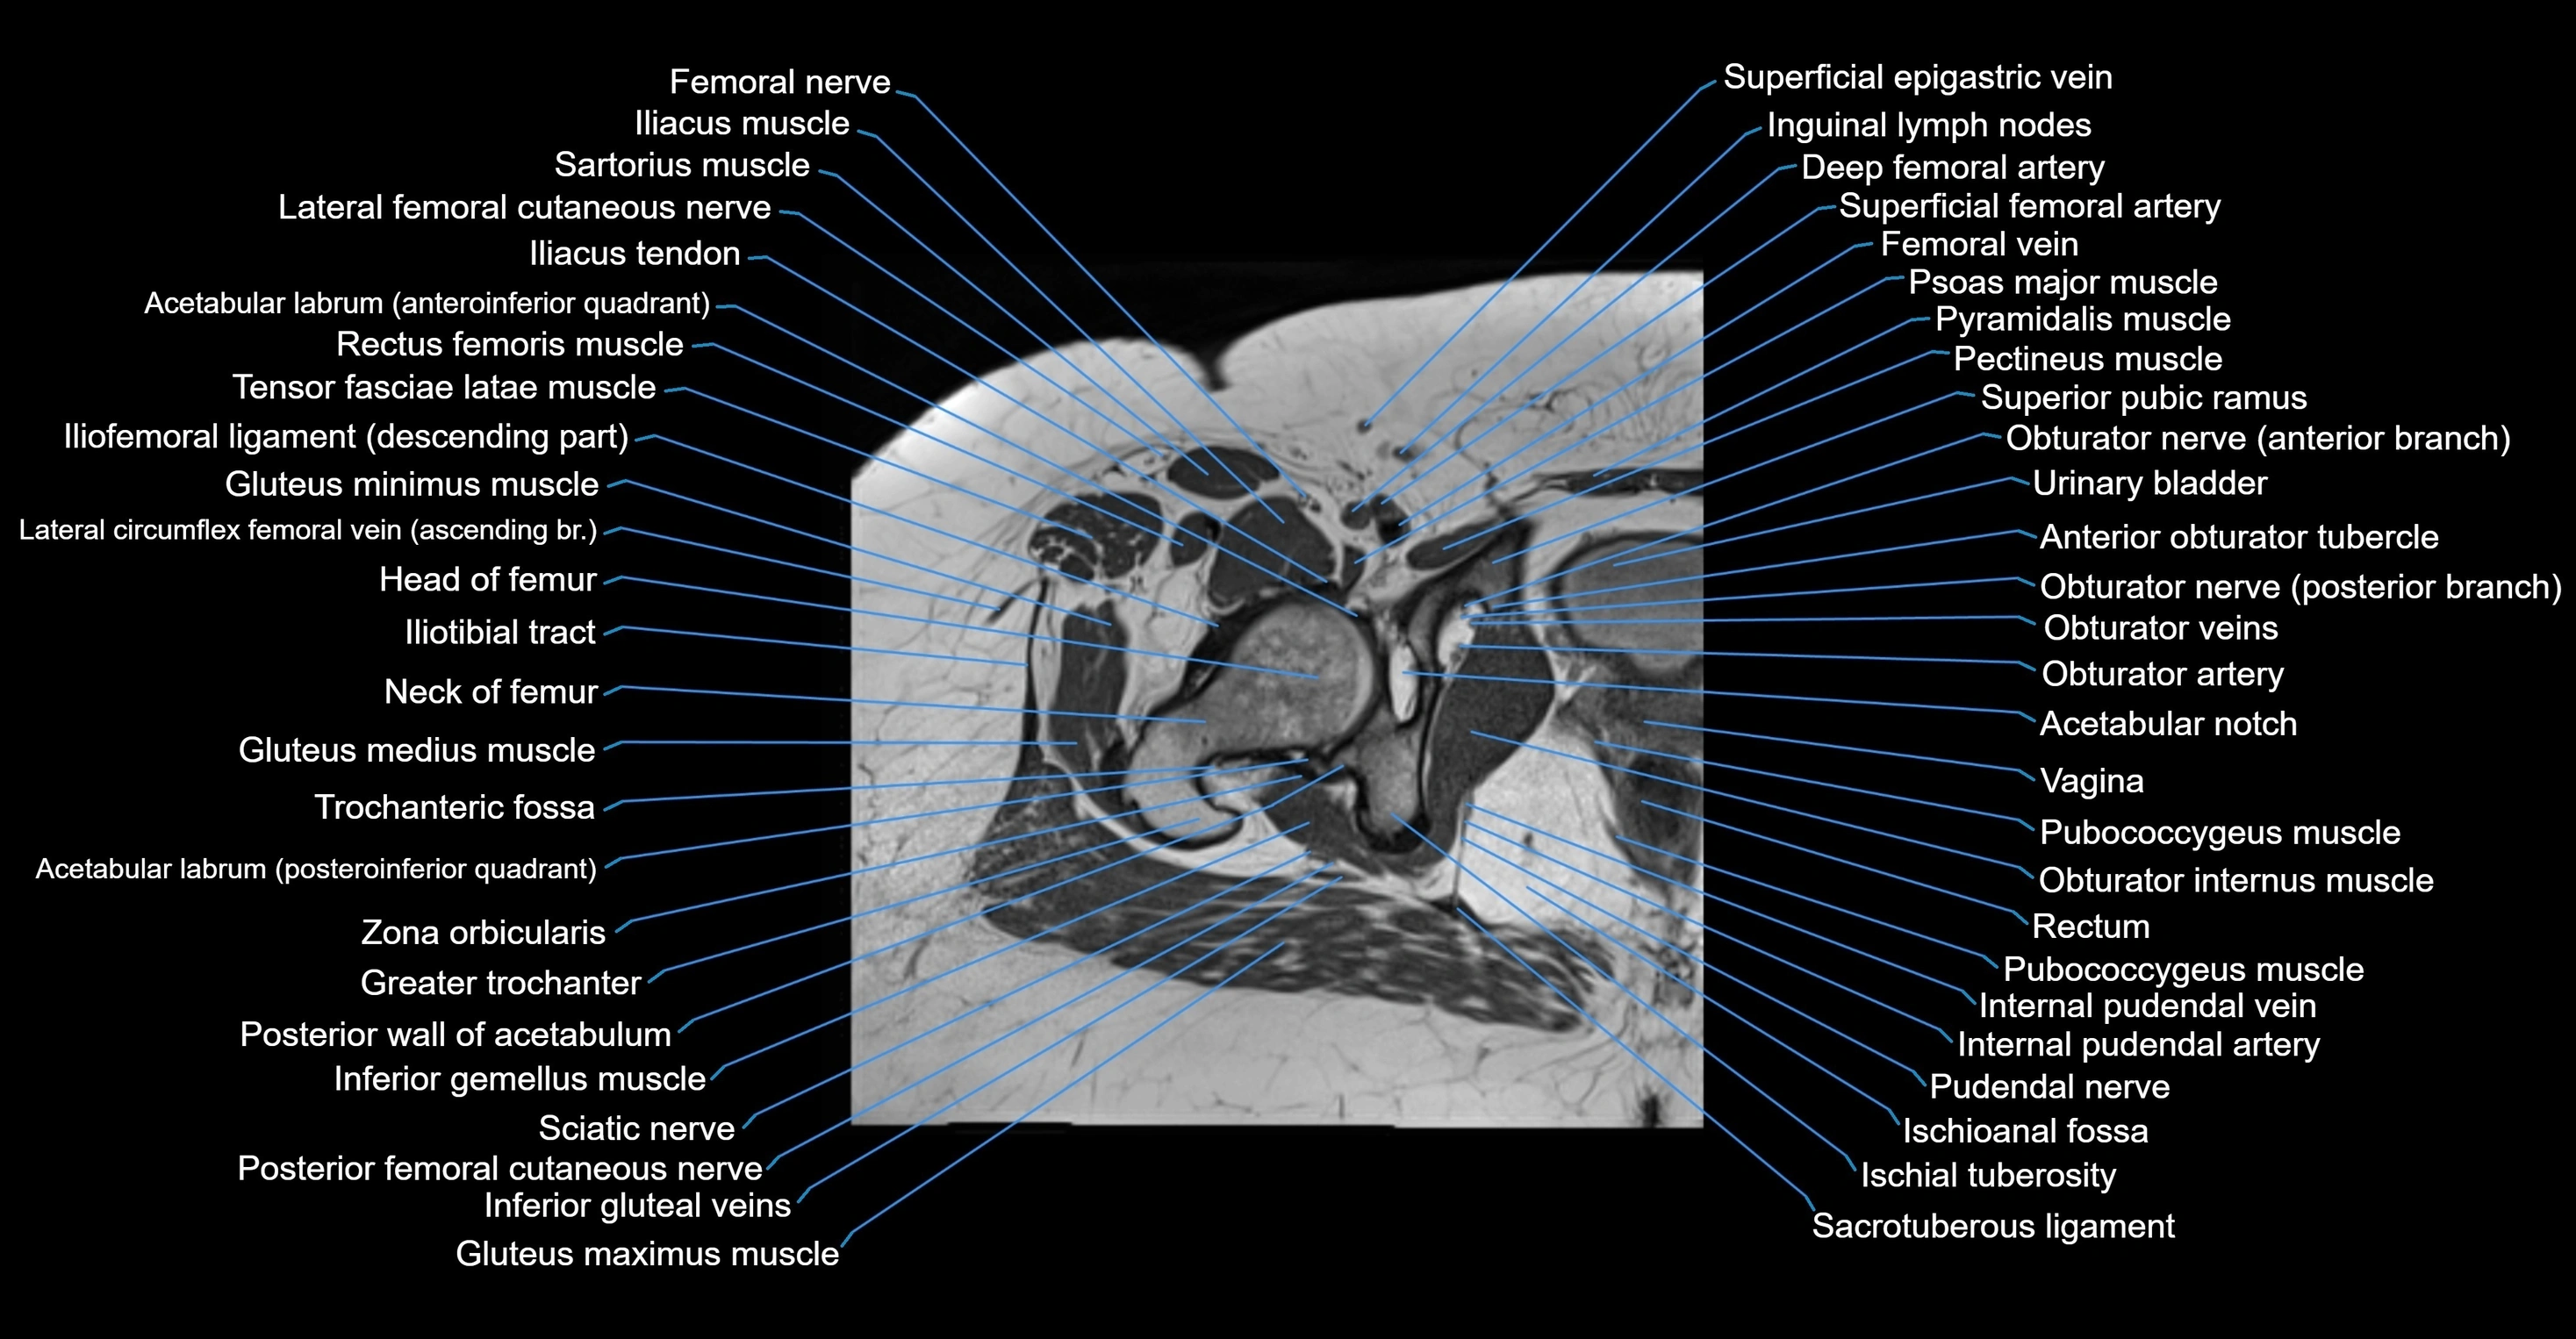

- Acetabular notch

- Acetabulum

- Head of femur

- Hip joint

- Neck of femur

- Obturator internus muscle

- Obturator internus tendon

- Obturator nerve

- Obturator vein

- Obturator veins

- Pubococcygeus muscle

- Pudendal nerve

- Rectum

- Sacrotuberous ligament

- Urinary bladder

- Vagina